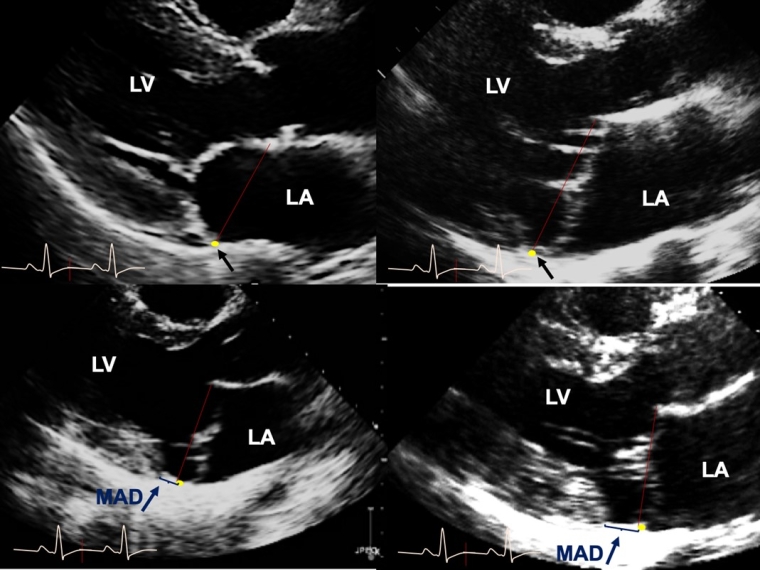

Echocardiographic morphologic features of AMVP are severe myxomatous degeneration, defined by thick and redundant leaflets with multisegment bileaflet MVP and MAD [5,6,12] (Figure 1). Importantly, bileaflet MVP, quite prevalent among patients with MVP, is not independently an SCD trigger in large cohorts or population-based studies [3]. Conversely, MAD with MVP is independently linked with ventricular arrhythmias at diagnosis or develops during follow-up [10]. Whether MAD distance predicts more frequent arrhythmias is unclear as are MAD-associated arrhythmia mechanisms, although myocardial fibrosis is often noted with longer MAD and hypothesised as causative.

Figure 1. Mitral valve prolapse and mitral annulus disjunction by transthoracic-echocardiography.

(Upper-row left) The transthoracic echocardiographic long-axis view in end-systole displaying normal mitral valve without MVP, (upper-row right) with myxomatous bileaflet MVP but no MAD, and myxomatous MVP with MAD of 4 mm length (lower-row left) and of 12 mm length (lower-row right). The red line characterises the mitral annular plane, the yellow dot with single black arrow the insertion of the posterior mitral leaflet mitral annulus and the single blue arrow MAD.

LA: left atrium; LV: left ventricle, MAD: mitral annulus-disjunction; MVP: mitral valve prolapse

Reproduced with permission from Eur Heart J 44(33): 3121-3135.